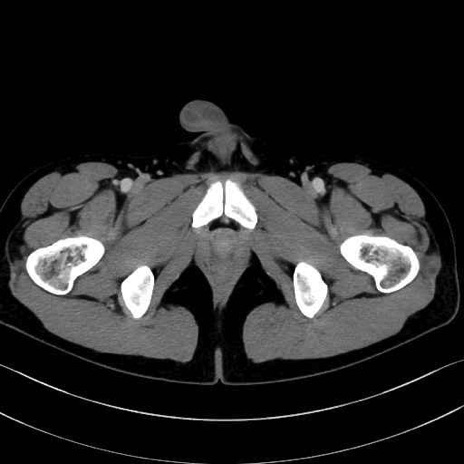

5. 大腿前面(大腿四頭筋群・伸筋群)

縫工筋 (Sartorius)

大腿直筋 (Rectus femoris)

外側広筋 (Vastus lateralis)

中間広筋 (Vastus intermedius)

6. 大腿内側(内転筋群)

恥骨筋 (Pectineus)

長内転筋 (Adductor longus)

短内転筋 (Adductor brevis)

大内転筋・小内転筋 (Adductor magnus / Adductor minimus)